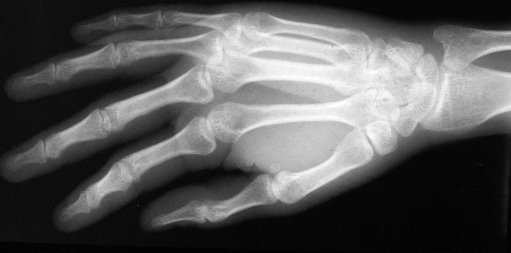

Standard Xray views: oblique hand

Xray beam angle 90 degrees.